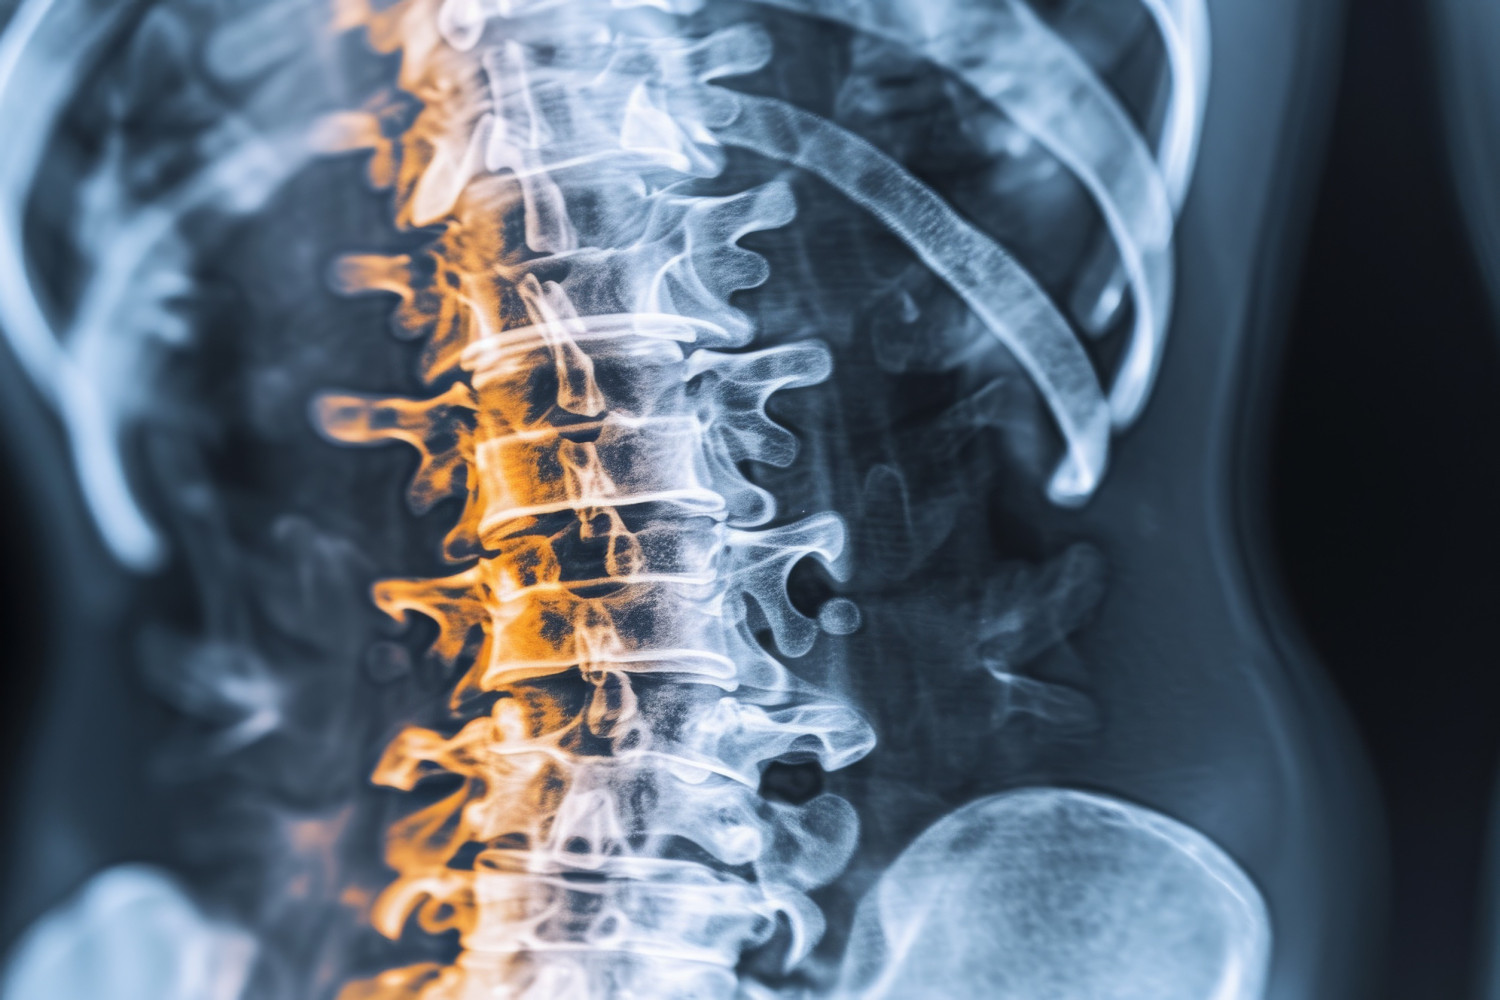

Задача изобретения – повышение эффективности лечения детей с диастематомиелией путем выполнения остеотомии дуг позвонков в проекции костной перегородки позвоночного канала. Направитель помогает врачам точно определить зону, где необходимо сделать разрезы в проекции позвонков, чтобы удалить костную перегородку. Планируется, что это поможет уменьшить травматичность хирургического вмешательства, а также будет способствовать сокращению сроков операции и профилактики развития деформаций позвоночного столба в процессе роста ребенка.

| На рисунке 1 представлен индивидуальный навигационный направитель для выполнения остеотомии дуг позвонков при удалении костной перегородки позвоночного канала при диастематомиелии, вид сзади, где: поз. 1 – позвоночник пациента с костной перегородкой позвоночного канала (вид сзади); поз. 2 – каркас, повторяющий рельеф наружной поверхности дуг позвонков; поз. 3 – отверстия, выполненные с возможностью фиксации направителя к кости спицами; поз. 4 – полый тубус-направитель для проведения остеотомии. |